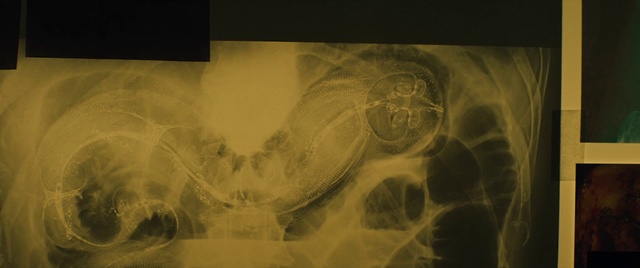

Best Video References: Stomach ache

Featured videos selected by a smart neural network algorithm